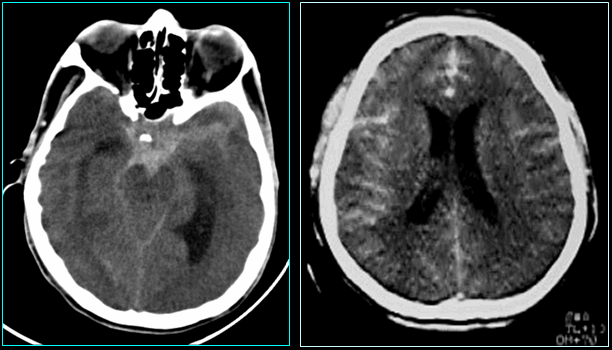

Chụp cắt lớp vi tính (CT Scan), chọc dò tủy sống làm xét nghiệm có thể được thực hiện để loại trừ chảy máu nhỏ.

Xét nghiệm công thức máu toàn bộ (CBC), bảng chuyển hóa toàn diện (CMP), điện tâm đồ (EKG), chụp cộng hưởng từ (MRI) và X-quang.

Chụp mạch máu não.